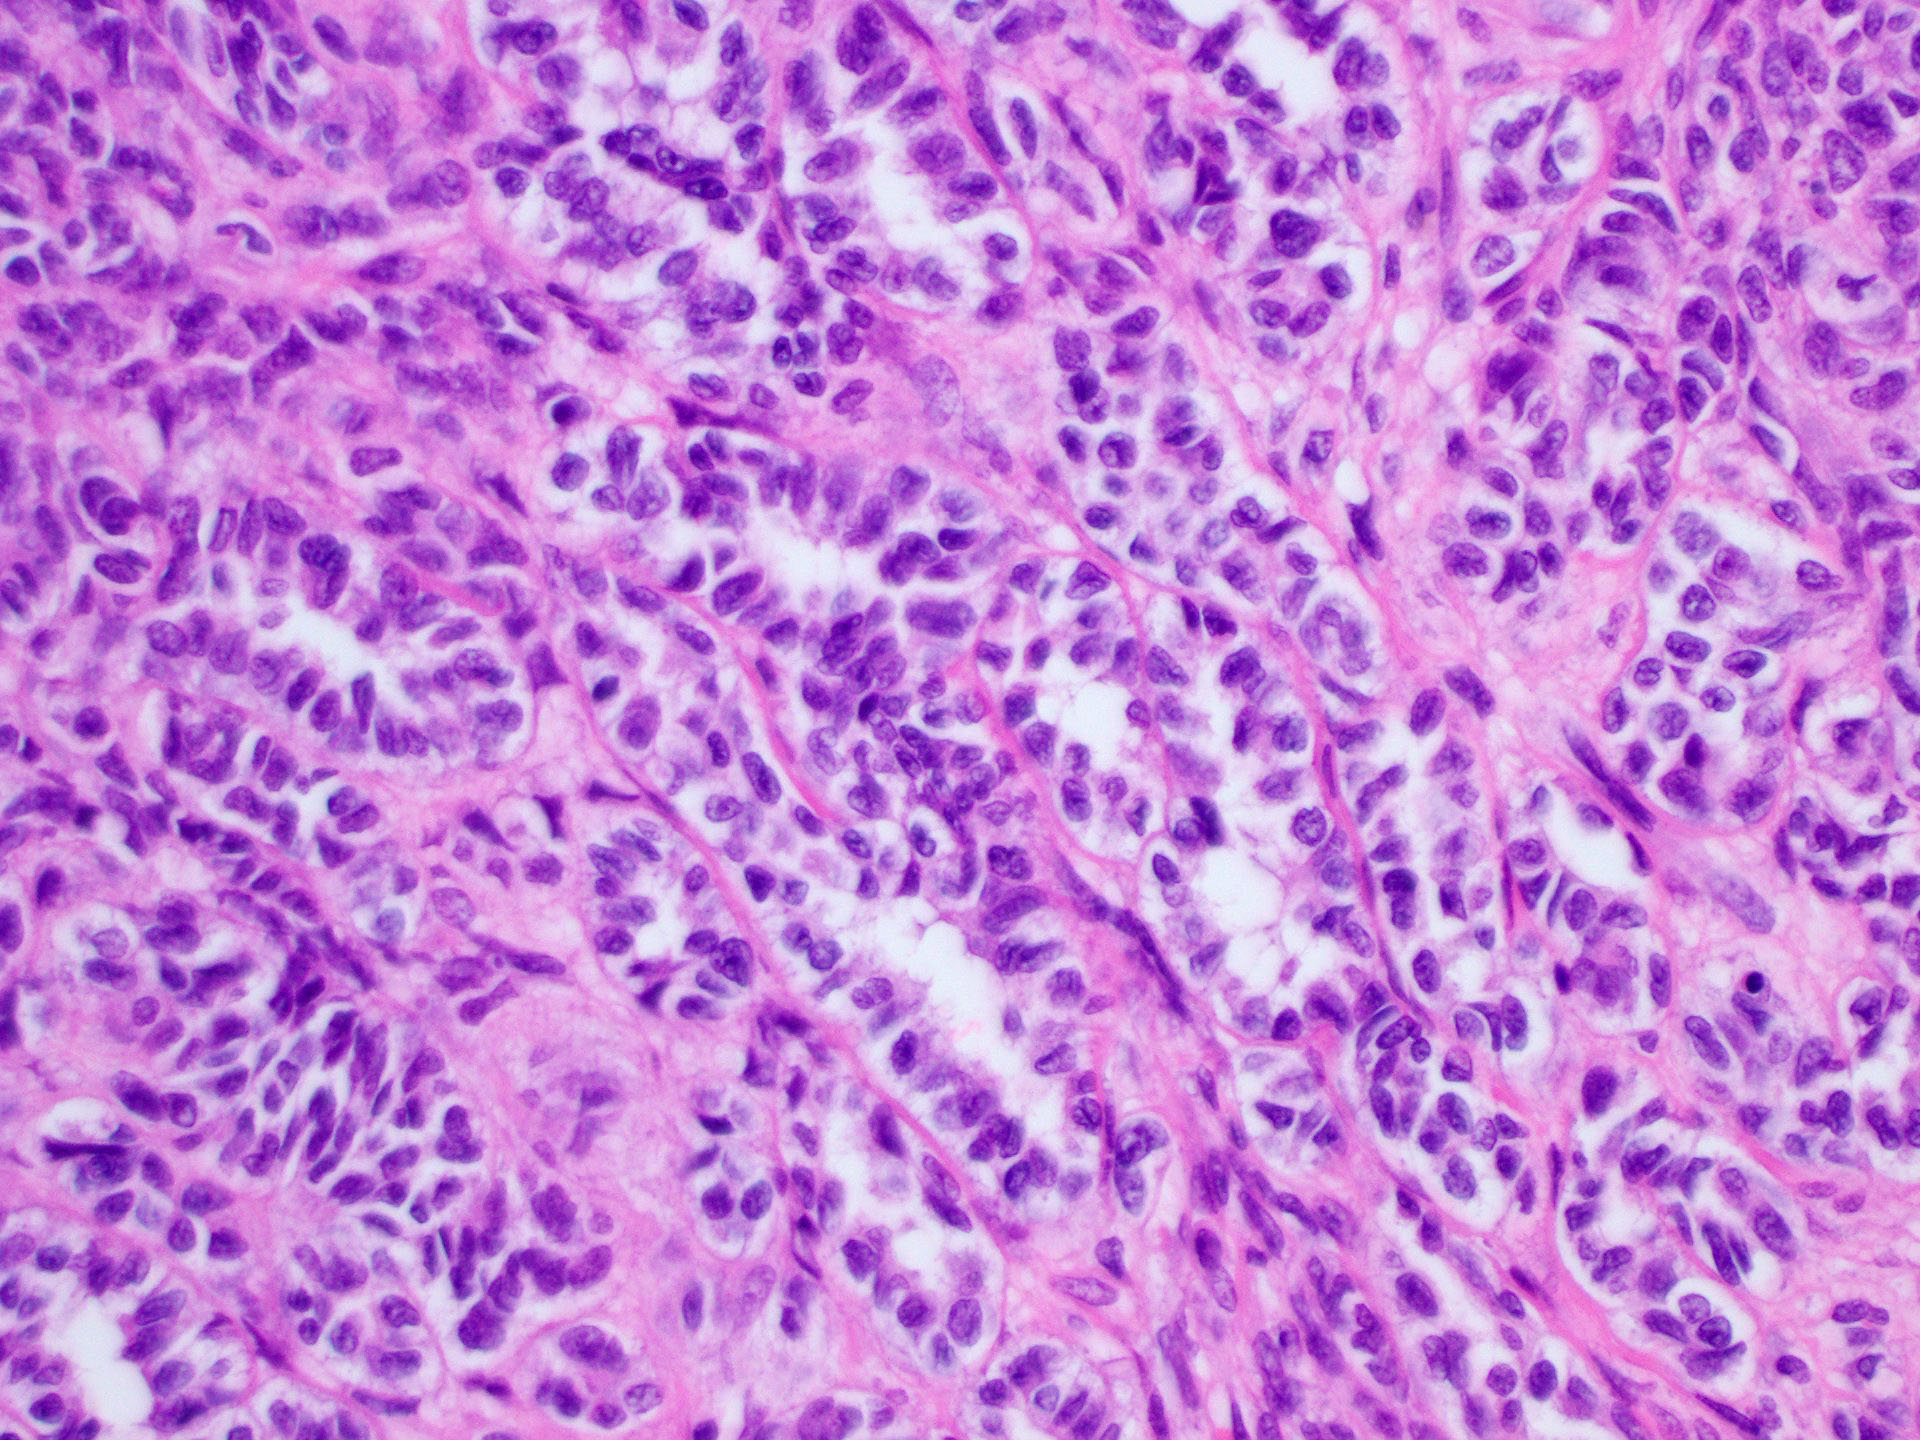

Microscopic (histologic) description

- Tubular pattern (most common and usually present at least focally) with solid or hollow tubules

- Cuboidal or columnar cells

- Bland oval to round, monotonous nuclei

- Pale cytoplasm

- Other patterns: trabecular, diffuse, alveolar, pseudopapillary, reniform, pseudoendometrioid, spindled

- Absent to very rare Leydig cells

- Pathologic features predictive of malignant behavior include 5 mitoses per 10 high power fields, severe cytologic atypia, necrosis and size > 5 cm